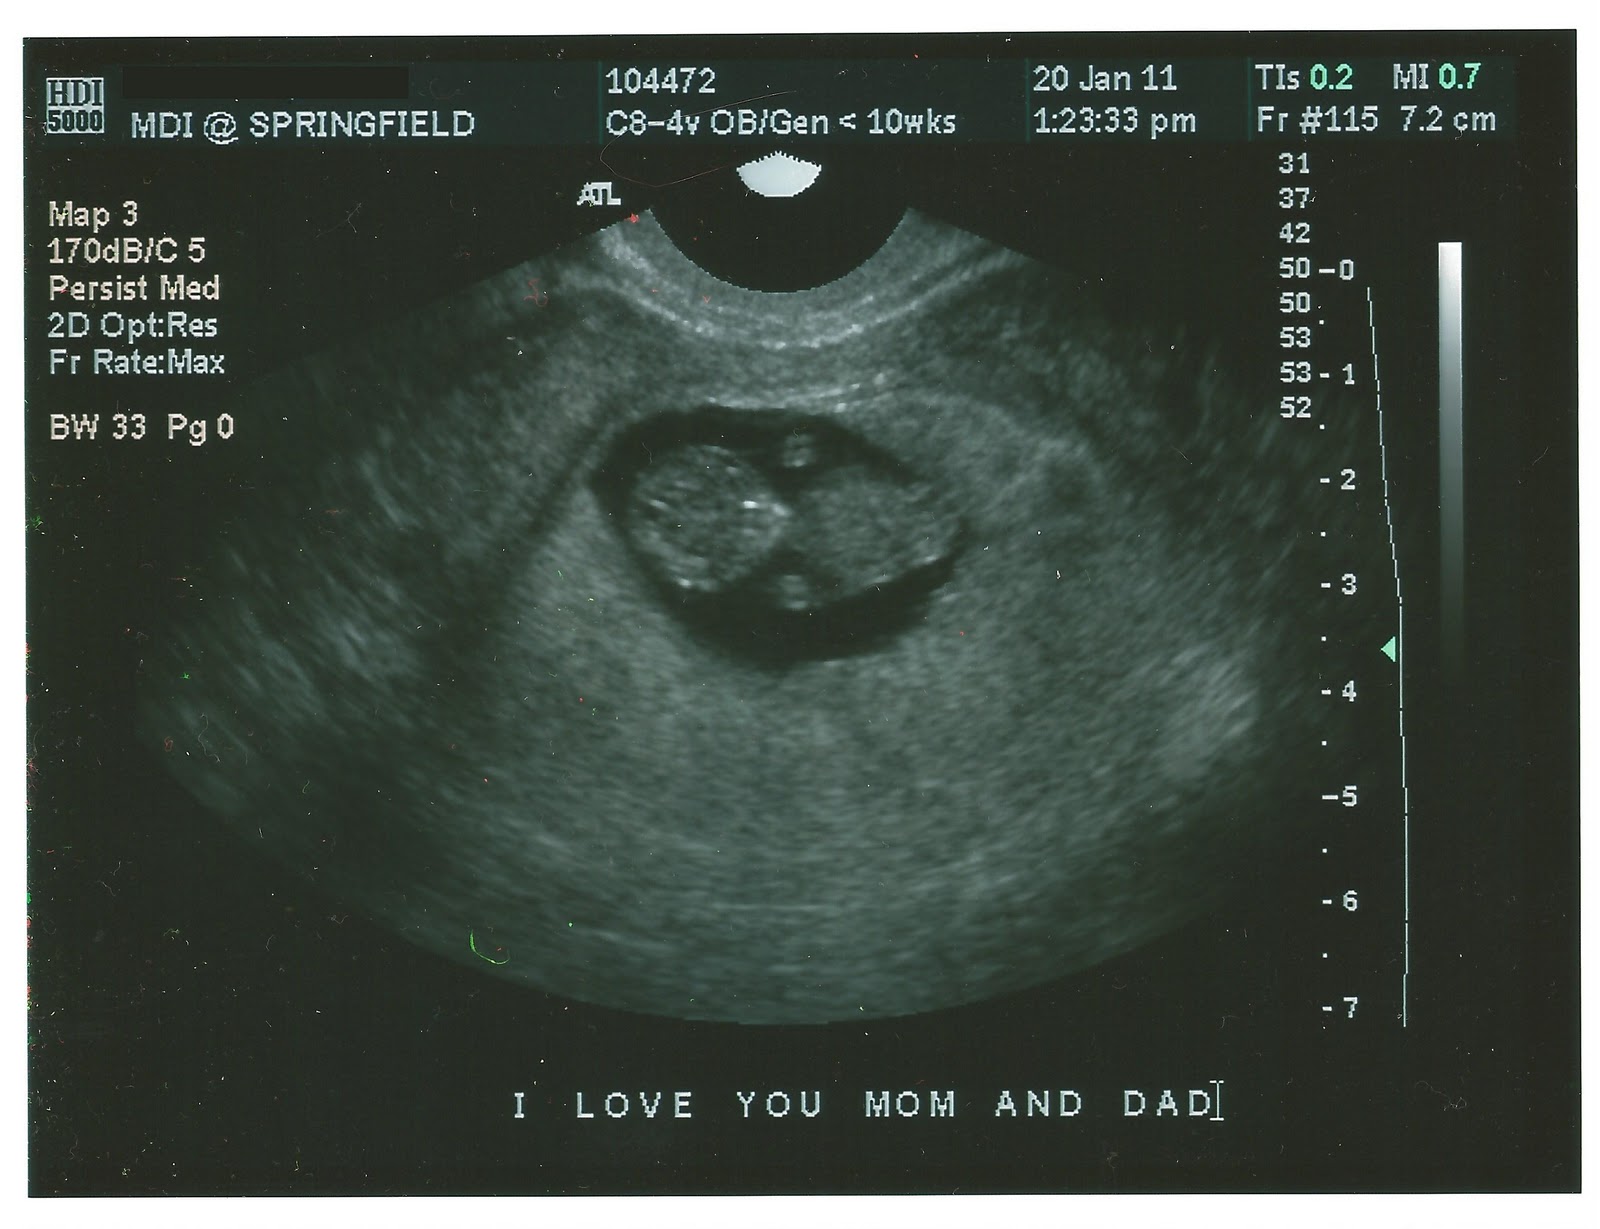

Yesterday I saw your face for the first time.

I watched you wiggle on the camera, and even the technican said, "Oh wow - look at that baby moving!" I explained to her that you were dancing. I think she rolled her eyes.

And so you did, moving your little head and your tiny arms. I saw what will someday be your little nose, and I watched your heart flicker on the screen - 171 beats a minute! I could have sat and looked at you all day.

When finally we were finished, I got dressed and went out to find your Daddy in the waiting room. He looked so worried, and I realized that he didn't even know that you were just fine! I quickly pulled out the photos and showed him the first pictures of his new baby. Someday when you're older you'll probably be embarrassed to know that we cried a little looking at your sweet face.